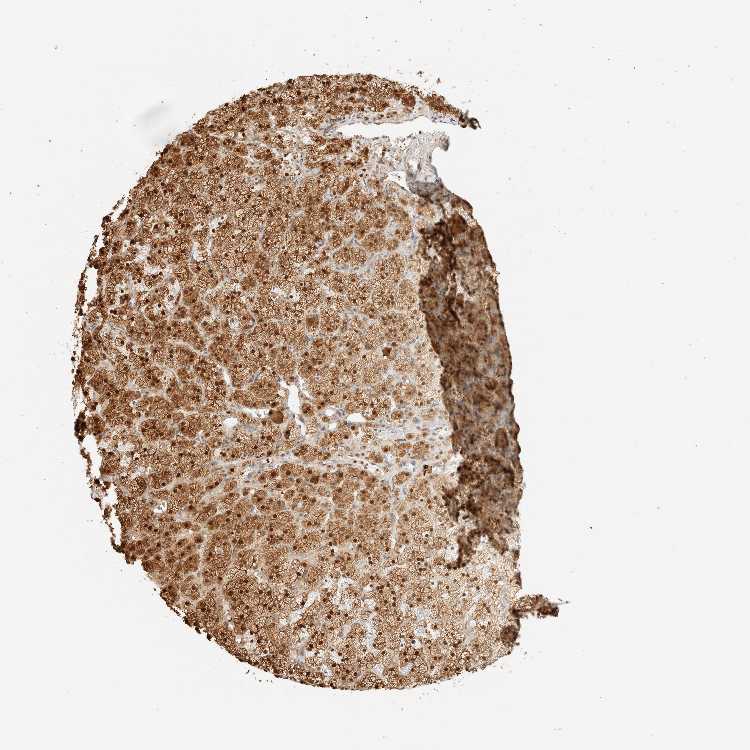

ADRENAL GLAND - Antibody stainingi

Antibody staining in the annotated cell types in the current human tissue is reported as not detected, low, medium, or high, based on conventional immunohistochemistry profiling in selected tissues. This score is based on the combination of the staining intensity and fraction of stained cells.

Each image is clickable and will lead to virtual microscopy that enables deeper exploration of all samples and also displays staining intensity scores, fraction scores and subcellular localization as well as patient and tissue information for each sample.

Antibody HPA023438

Glandular cells High